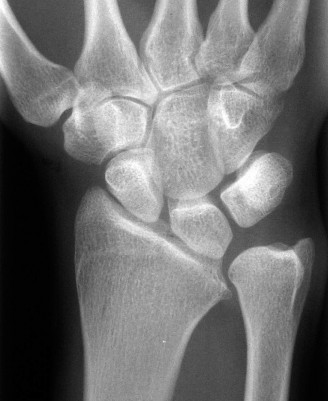

Imaging Carpal Collapse

For the second patient, standard PA radiographs immediately reveal the diagnosis. We observe the classic Terry Thomas sign—a widening of the scapholunate interval greater than 3 mm. Furthermore, the lateral radiograph demonstrates a Dorsal Intercalated Segment Instability (DISI) deformity, characterized by a radiolunate angle greater than 15 degrees (lunate extended) and a scapholunate angle greater than 60 degrees.

Advanced imaging, particularly Computed Tomography (CT), is highly beneficial for preoperative templating. A fine-cut CT scan accurately maps the extent of the degenerative changes. In scapholunate advanced collapse (SLAC), arthritis follows a highly predictable, sequential pattern. It begins at the radial styloid-scaphoid articulation (Stage I), progresses to involve the entire radioscaphoid fossa (Stage II), and eventually encompasses the capitolunate joint as the capitate migrates proximally into the widened SL gap (Stage III). Notably, the radiolunate joint is universally spared in SLAC wrist due to the concentric, congruent nature of the lunate fossa and the preservation of the short radiolunate ligaments.